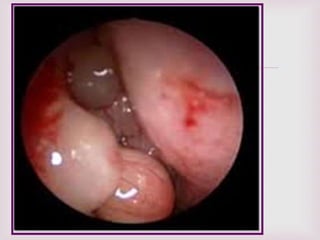

EXPLORACIÓN FÍSICA.

 Tumores con aspectos de uva.

 Se pueden encontrar en ambas fosas

nasales.

 Pueden adoptar la forma de la región

anatómica donde se encuentran.

 Blandos, tersos, translucidos.

 Ulceraciones con sangrado en ocasiones.

 Se encuentran en la parte superior de la

cavidad nasal y proceden del complejo

osteomeatal.

 La rinoscopia anterior

confirmara la presencia

de pólipos.

 Características macroscópicas de

los pólipos nasales…